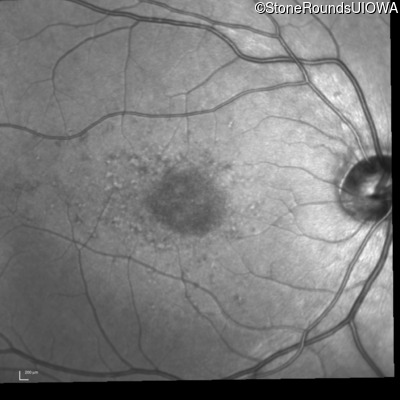

Fundus Photography - Right - 20/80 -1

Exemplar